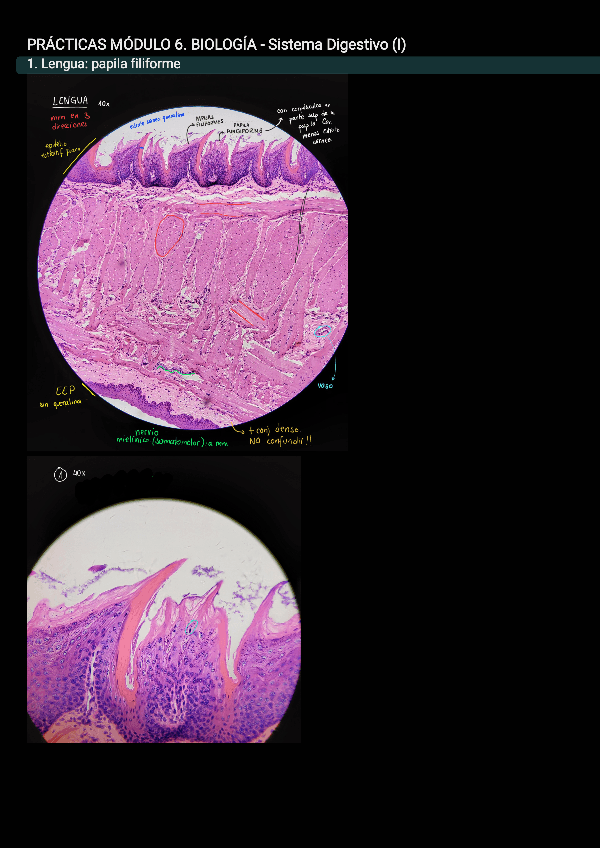

He publicado nuevos apuntes de 3º Bioquímica Clínica y Genómica Funcional Humana: practicas-bio-m6.pdf

11 páginas